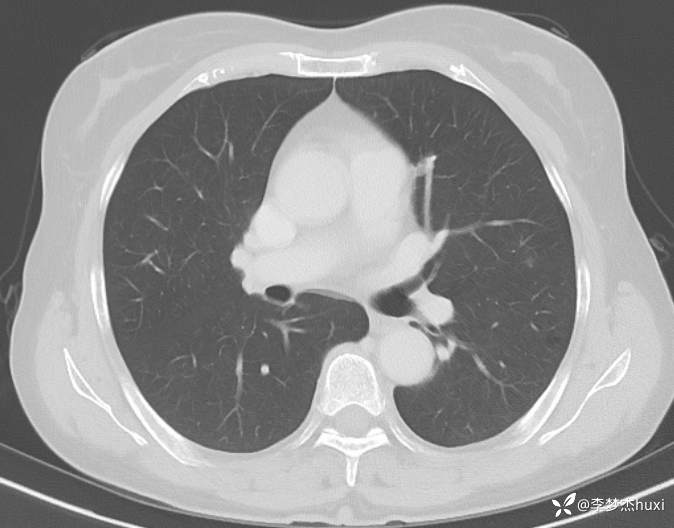

1.现病史:患者老年 女,患者于入院前3天(2024-06-02)体检查胸部CT:左肺部分实性结节,右肺磨玻璃结节,左肺上叶实性结节--性质?建议肺结节门诊会诊检查;双肺索条,双肺下叶条絮状高密度影--考虑肺血坠积效应,主动脉壁钙化,双侧胸膜局部增厚,左侧乳腺钙化点。2024-06-04查胸部增强CT:左肺上叶实性结节--占位?建议结合病理;左肺部分实性结节,右肺磨玻璃结节,建议肺结节门诊会诊检查;双肺索条,主动脉壁钙化,双侧胸膜局部增厚,左侧乳腺钙化点。患者目前无咳嗽、咳痰,无发热,无胸痛,今为求进一步诊治来我院,门诊以“肺诊断性影像异常”收入院。

4.辅助检查:2024-06-02查胸部CT:左肺部分实性结节,右肺磨玻璃结节,左肺上叶实性结节--性质?建议肺结节门诊会诊检查;双肺索条,双肺下叶条絮状高密度影--考虑肺血坠积效应,主动脉壁钙化,双侧胸膜局部增厚,左侧乳腺钙化点。2024-06-04查胸部增强CT:左肺上叶实性结节--占位?建议结合病理;左肺部分实性结节,右肺磨玻璃结节,建议肺结节门诊会诊检查;双肺索条,主动脉壁钙化,双侧胸膜局部增厚,左侧乳腺钙化点。。